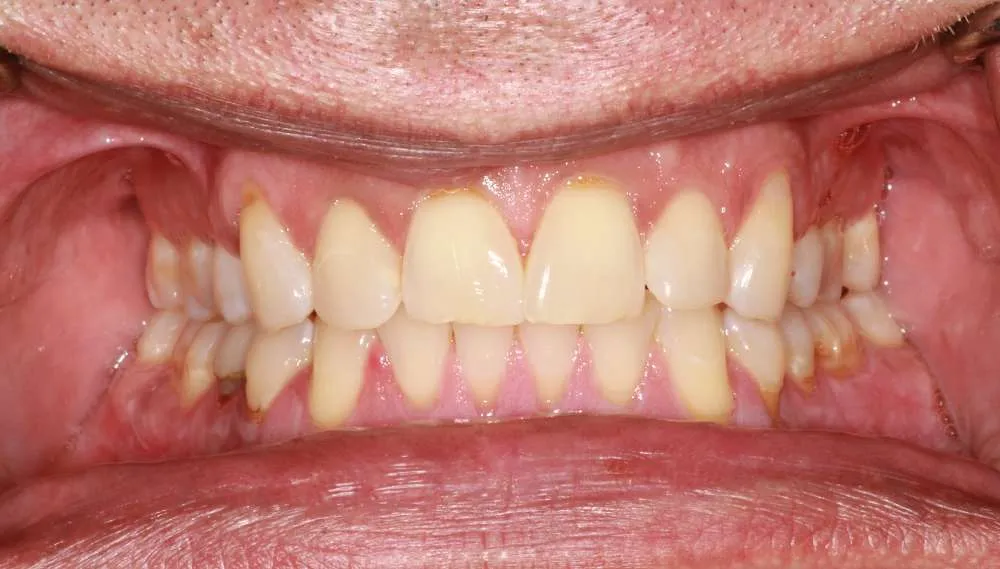

Real Stories, Real Results: Case Studies Showcasing How Our Personalized Approach Transforms Smiles and Lives

Witness the Remarkable Changes We Can Achieve

While ultra-thin veneers are a fantastic option for many patients looking to enhance their smile, they may not be suitable for everyone. Ideal candidates are those with healthy teeth and gums who are looking to correct cosmetic issues like discoloration, misalignment/crooked or small gaps. During your consultation, Dr. O'Malley will assess your dental health and determine if ultra-thin veneers are the right choice for you.